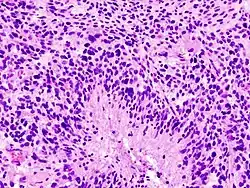

Les glioblastomes multiformes sont caractérisés par la présence de petites zones de tissu nécrosé entourées de cellules hautement anaplasiques. Cette caractéristique différencie la tumeur des astrocytomes de grade 3, qui ne possèdent pas ces zones de tissu nécrosé. Bien que le glioblastome multiforme puisse être issu d'astrocytomes de grades inférieurs, des autopsies post-mortem ont révélé que la plupart des glioblastomes multiformes ne sont pas causés par des lésions cérébrales antérieures.

Contrairement aux oligodendrogliomes (en), les glioblastomes multiformes peuvent se former dans la matière grise ou la matière blanche du cerveau, mais la plupart des GBM se forment au plus profond de la matière blanche et infiltrent rapidement le cerveau, devenant parfois très gros avant de donner des symptômes. La tumeur peut s'étendre à la paroi méningée ou à la paroi ventriculaire, entraînant une haute teneur en protéines du liquide cérébrospinal (LCS) (> 100 mg·dL-1) appelée hyperprotéinorachie, et occasionnellement une pléiocytose (en) de 10 à 100 cellules, en majorité des lymphocytes. Les cellules malignes présentes dans le liquide cérébrospinal peuvent s'étendre à la moelle épinière ou causer une gliomatose méningée. Cependant, les métastases du GBM au-delà du système nerveux central sont extrêmement rares. Environ 50 % des GBM occupent plus d'un lobe d'un hémisphère ou sont bilatéraux. Les tumeurs de ce type naissent généralement dans le cortex, et peuvent traverser le corps calleux, produisant un gliome « papillon » (bilatéral).